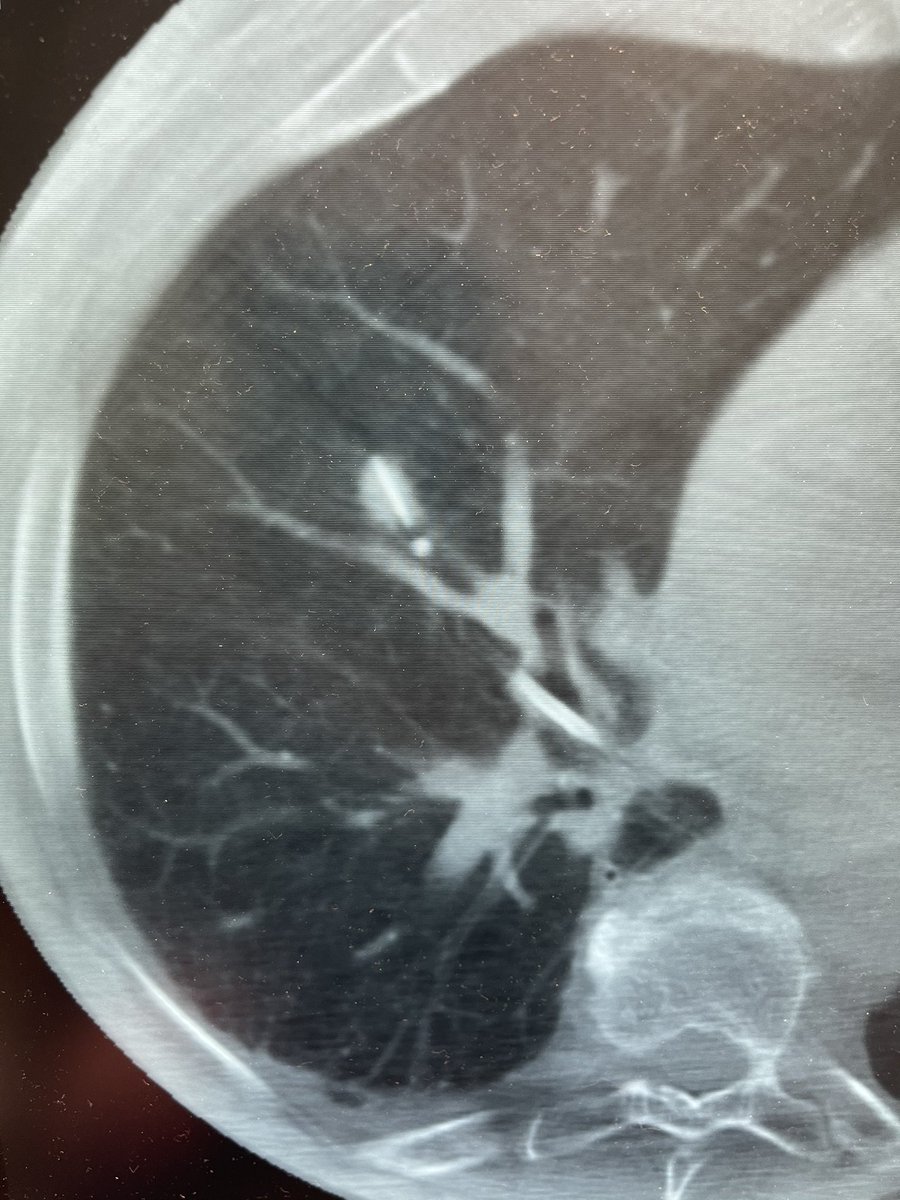

Ramsy Abdelghani, MD@Rabdelgh·

Growing LUL pleural based lesion with no airway leading to it and negative on IR biopsy. Was able to navigate close (within 2cm) to the lesion, biopsy, and adjust using CBCT. Positive for poorly differentiated carcinoma. I would have never tried this without CBCT and Robotics.